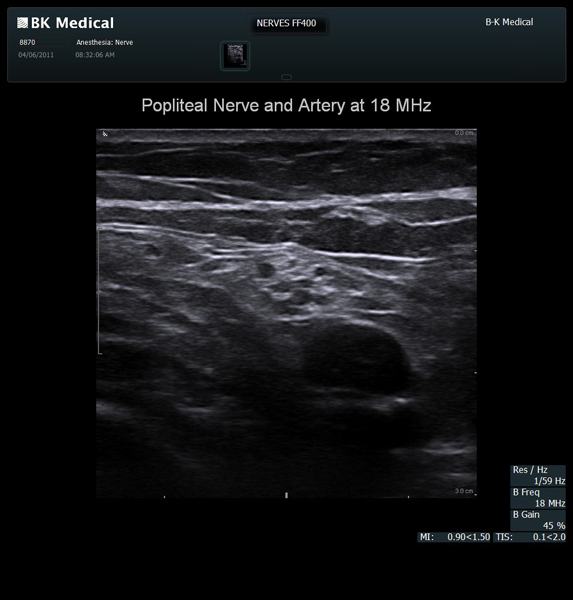

The Flex Focus 400 exp ultrasound system offers premium image quality with fast frame rates for excellent temporal resolution. The system features Automatic Mode Adjustment (AMA) to optimize high resolution B-Mode Imaging when changing modes and depth.

Transducers Designed for Guidance

BK Medical offers high-frequency linear transducers, imaging from 18-2 MHz for upper and lower extremities, and curved array abdominal transducer 8820e for special deep nerves or paravertebral/spinal applications. Our transducers provide superb detail that makes it easy to see your needle during procedures.